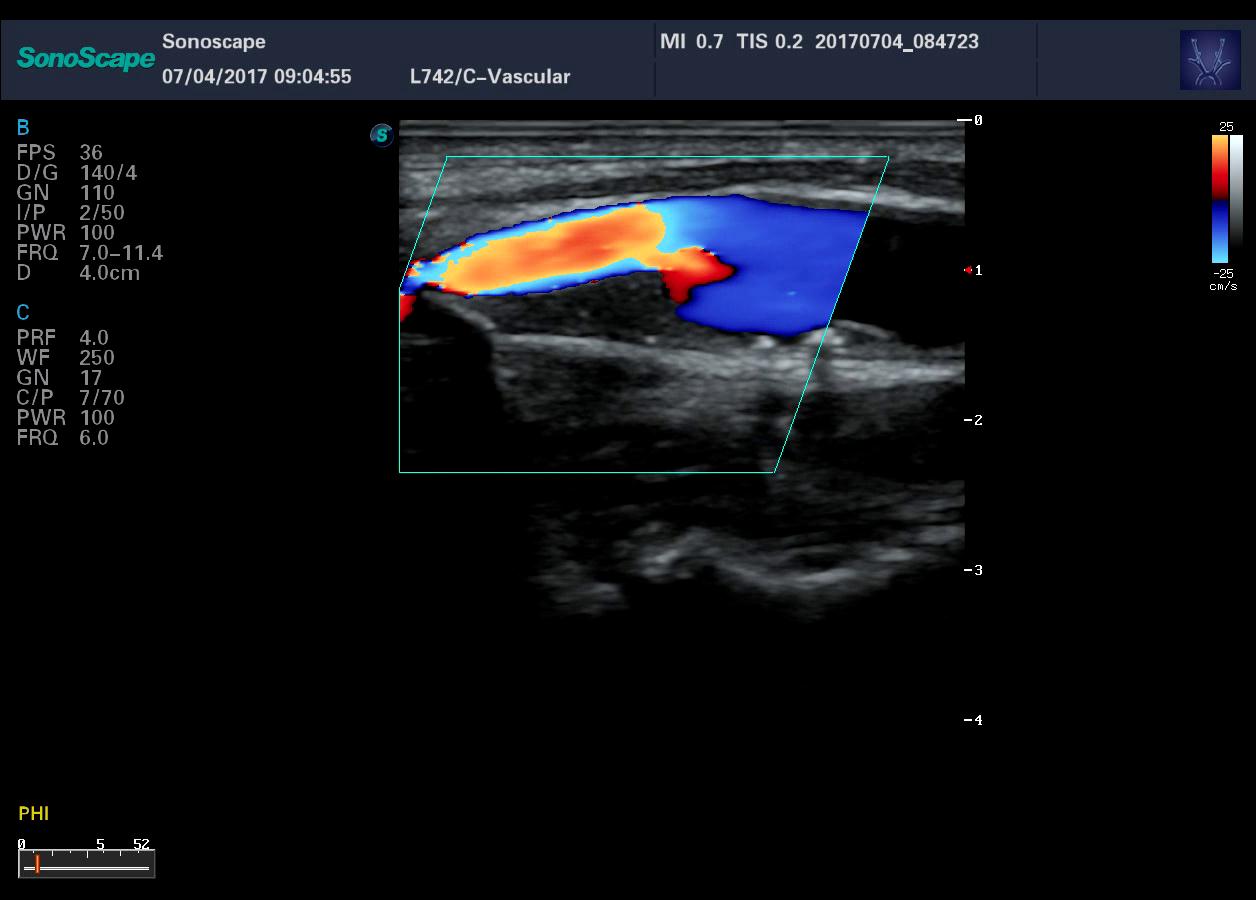

- Три технологии сосудистой визуализации – SRF, Bright Flow, Micro F для уверенной визуализации самых мелких сосудов